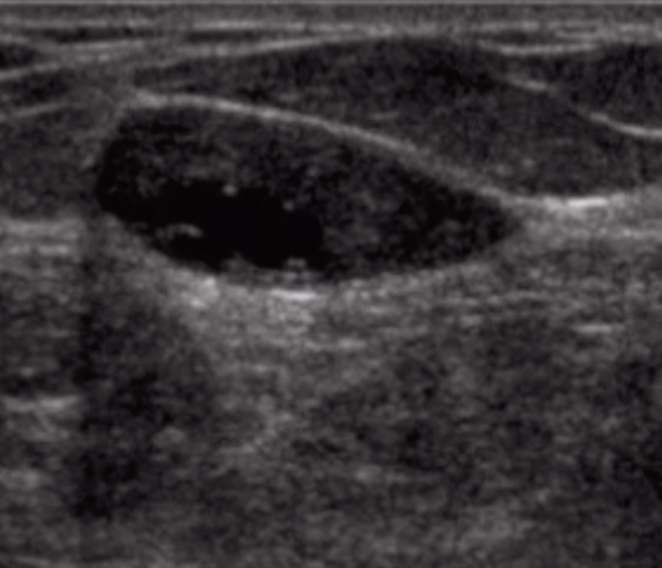

Galactocele

• Subareolar

• Fluid-fluid level on US

• Only seen in lactating patient

• Do not biopsy - can cause milk fistula